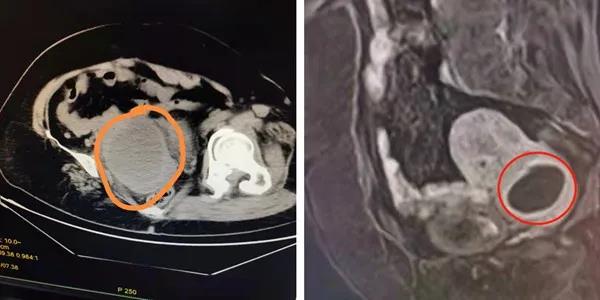

7月11日,患者张阿姨初至某三甲医院急诊就诊,查CT提示子宫体积明显增大,可见10*6.9cm类圆形低密度影,查彩超却提示左附件区低回声74*71mm,与子宫分界不清。住院抗炎治疗半个月,出院前复查彩超,仍提示包块位于左附件处。但是当张阿姨于一个月后来到我院再复查阴道彩超时,结果又提示子宫下段囊性包块,直径约4cm。通俗来说,就是初诊时CT提示“异物”在子宫腔内,彩超提示“异物”在子宫外围附件上,而一个月之后我院复查阴道彩超又提示“异物”到了子宫颈处。这到处“移动”的盆腔肿物,实在不常见,为进一步诊治,顾爱玲主任将张阿姨收住了院。

入院后,为进一步确认张阿姨的情况,行盆腔增强磁共振,提示:子宫下段宫颈前壁肌层内病灶,约4公分,不排除脓肿。完善各项术前检查,顾爱玲主任诊查病人后分析:患者发病已有一月,起病有发热、外院抗感染治疗有效,考虑盆腔感染明确。但几次检查结果均不一致,这移动的、会跑的盆腔包块,究竟是什么?实属罕见!

△图左:查急诊CT提示宫腔内病灶

△图右:增强磁共振MRI提示宫颈肌层内病灶